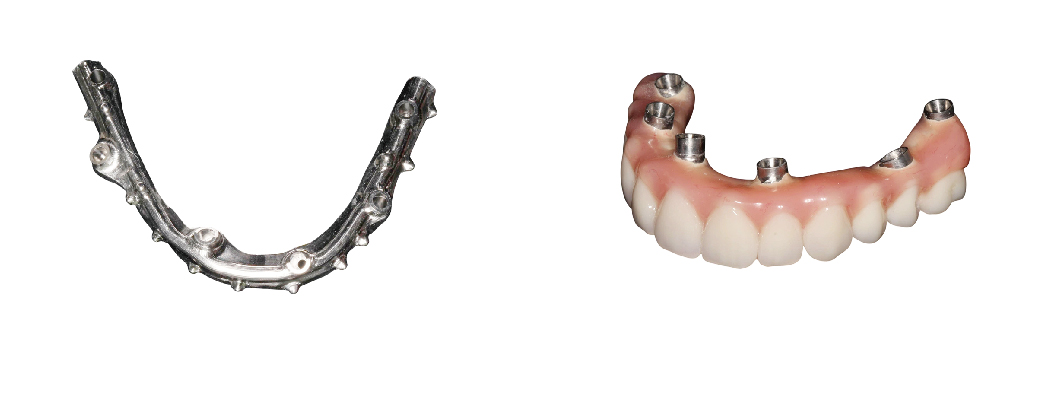

只需上、下顎各四支或六支植體支撐,由於所需的植體較少,牙縫也少,因此清潔較容易。 其中兩支植體的傾斜度即能替代牙橋,提供穩固的支撐力,減少補骨的需求。 與傳統植牙相比,減少手術次數,縮短治療週期。 最快當日即可裝戴臨時固定式假牙,恢復正常生活, 模仿天然骨頭隆起的形狀,重現自然的唇形,擬真人工牙齦,減少齒間黑三角更美觀, 堅持使用Procera原廠鈦合金連桿,高品質且密合度佳。

金屬支架比一比

堅持使用NobelProcera

NobelProcera Implant Bar Overdenture(#IBO),由技師透過先進的CAD/CAM技術進行掃描設計,確保每個步驟的精確性和一致性。

設計完成後,數據檔案會被迅速、安全地傳輸到美國工廠,進行高精度的加工銑削製作,這個過程不僅大幅縮短了等待時間,還提高了最終產品的精度與品質。